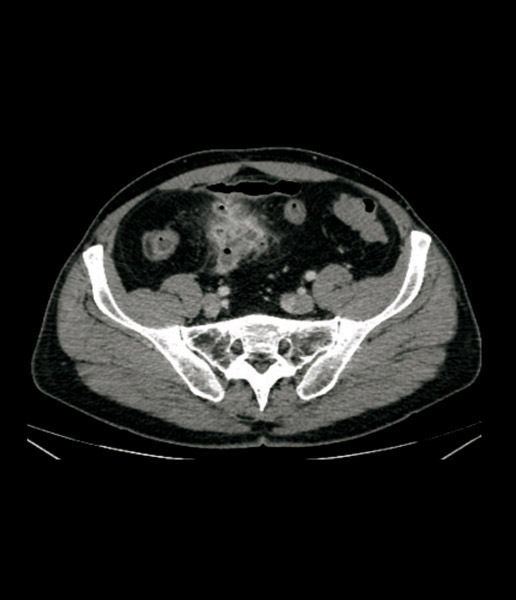

Aspect de collection hydro-aérique au contact de l’iléon correspondant à un abcès, avec hyperhémie du méso (signe du peigne).